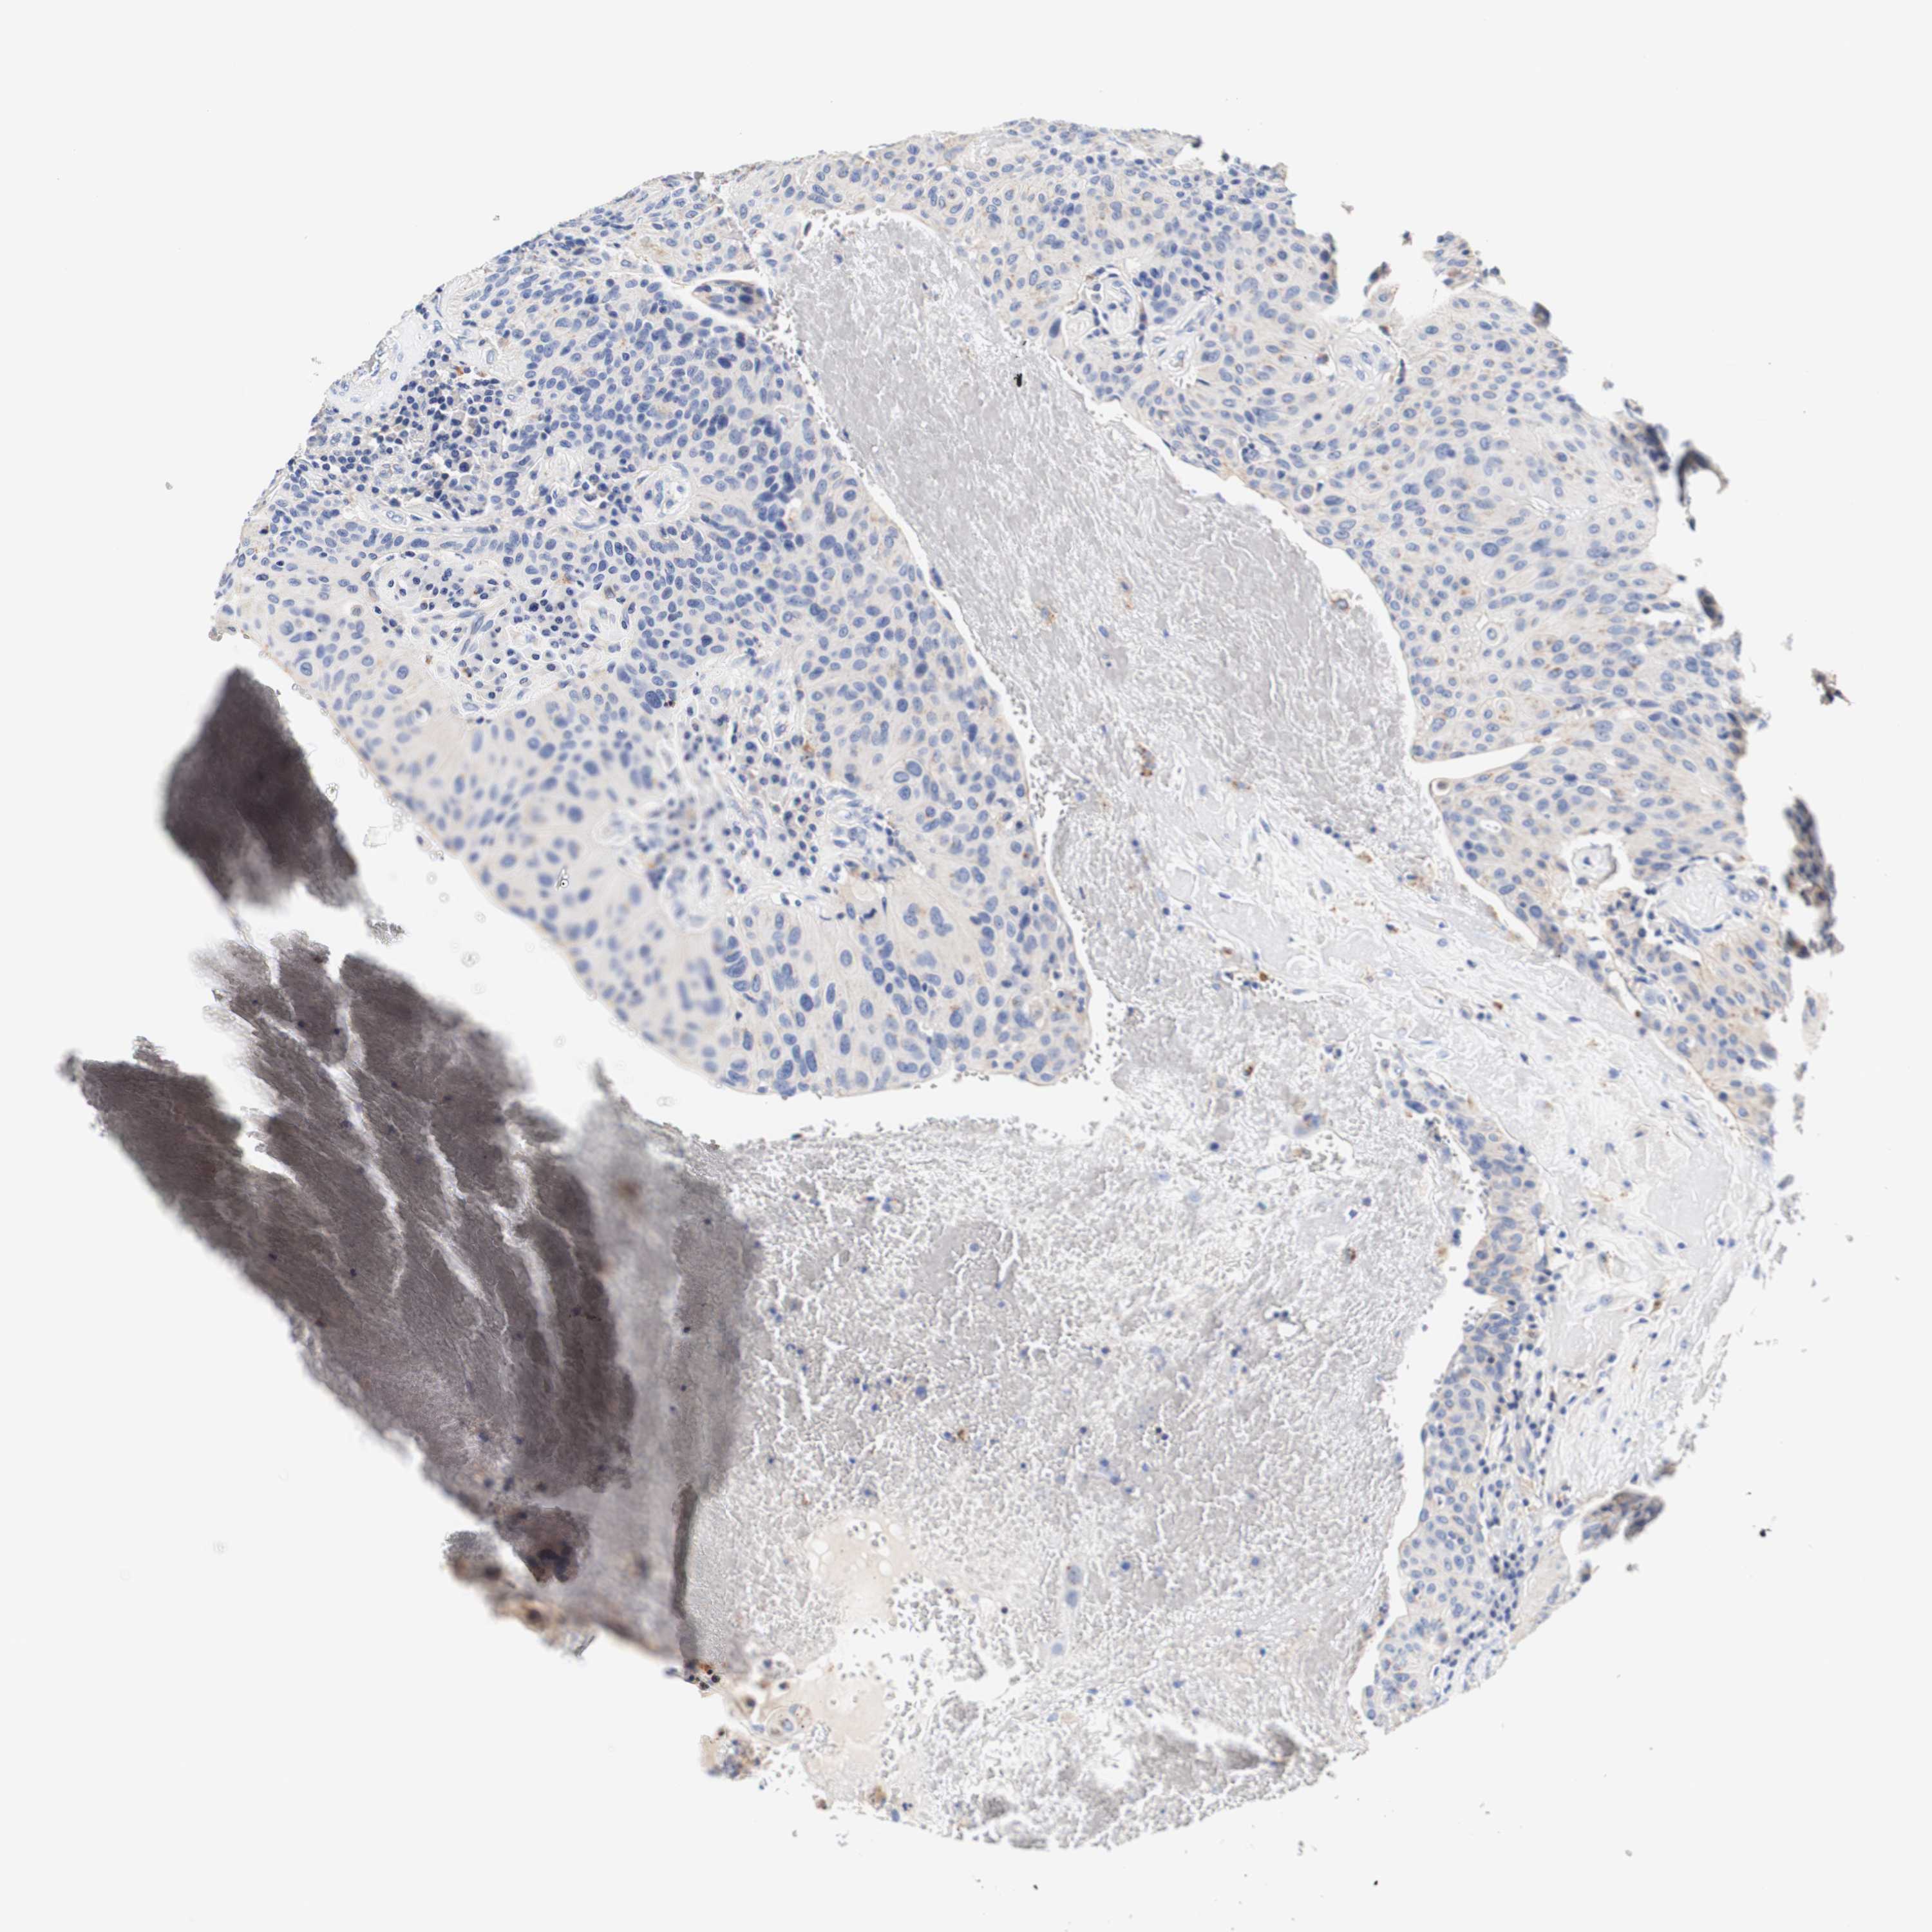

UROTHELIAL CANCER - Protein expressioni

A mouse-over function shows sample information and annotation data. Click on an image to view it in a full screen mode. Samples can be filtered based on level of antibody staining by selecting one or several of the following categories: high, medium, low and not detected. The assay and annotation is described here.

Note that samples used for immunohistochemistry by the Human Protein Atlas do not correspond to samples in the TCGA dataset.

Antibody stainingi

Antibody staining in the annotated cell types in the current human tissue is reported as not detected, low, medium, or high, based on conventional immunohistochemistry profiling in selected tissues. This score is based on the combination of the staining intensity and fraction of stained cells.

Each image is clickable and will lead to virtual microscopy that enables deeper exploration of all samples and also displays staining intensity scores, fraction scores and subcellular localization as well as patient and tissue information for each sample.

Antibody HPA011753

Antibody HPA017206

Antibody CAB004347

Staining

High

Medium

Low

Not detected

Intensity

Strong

Moderate

Weak

Negative

Quantity

>75%

75%-25%

<25%

None

Location

Nuclear

Cytoplasmic/membranous

Cytoplasmic/membranous,nuclear

Urothelial carcinoma, Low grade

Urothelial carcinoma, High grade